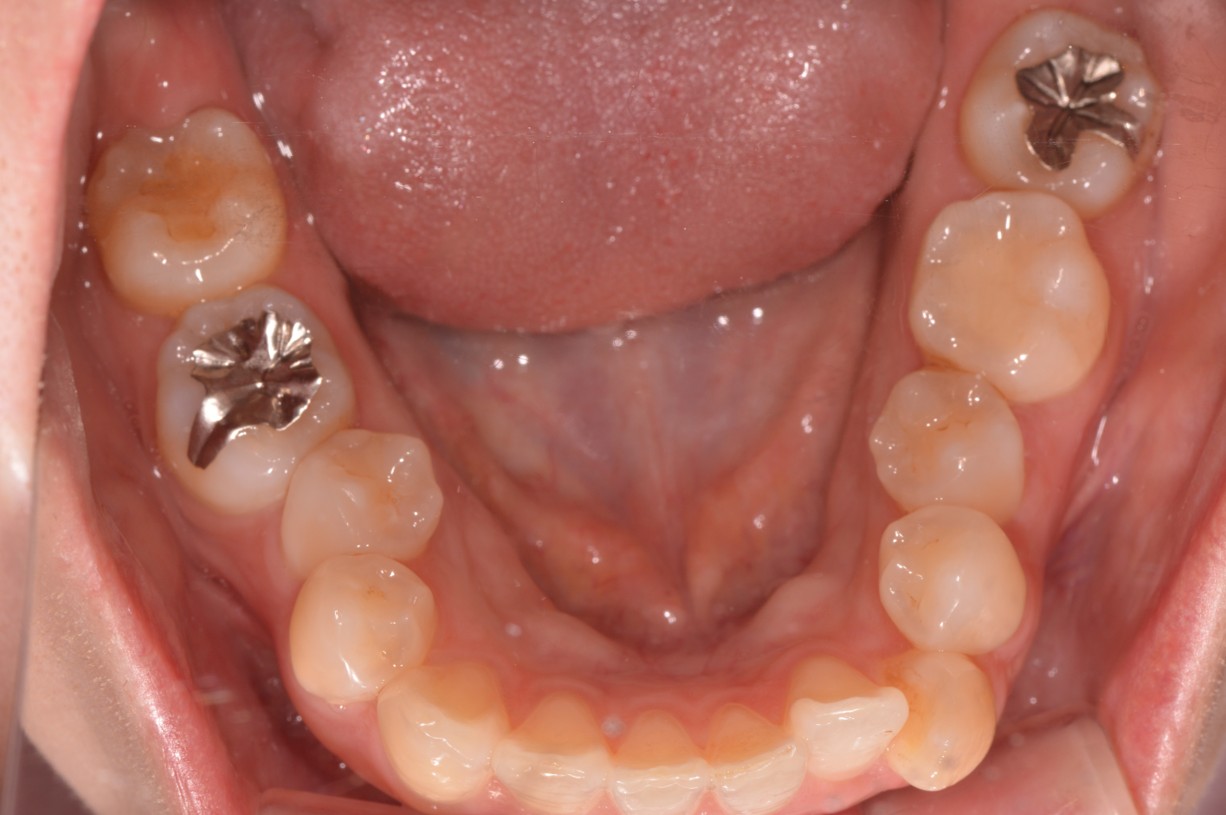

症例2

| 項目 | 詳細 |

|---|---|

| 患者様データ | 30代 女性 |

| 来院時の主訴 | 「右上の、内側に生えている歯が邪魔。」 |

| 矯正法 | 上の歯2本、下の歯2本、親知らず3本を抜歯しての矯正 |

| 通院期間 | 3年6ヶ月 |

| 治療費 | 総額:1,230,000円(税抜) 【内訳】 精密検査50,000円、メタルワイヤー矯正800,000円、月に1度の調整料5,000円、後戻り防止のリテーナー35,000円×2 |

| リスクと副作用 |

①歯を動かす事による痛みがあります。また、装置に慣れるまでは、口内炎ができやすいです。 ②歯肉が退縮するリスクがあります。装置が全ての歯に付くので、ハミガキが難しくなります。 ③長期的なメインテナンスが必要 |

| ここがこだわりのポイント!☝ | こちらの患者様は上の歯が1本内側に生えていましたが、奥歯の噛み合わせの方が問題でした。ハサミ状咬合といい、奥歯が極端に外側に向いており、下の歯と噛み合っていない状態でした。ハサミ状咬合は長期的にみると、前歯に大きな負担がかかったり、磨きにくい事による虫歯や歯周病になりやすいなどのリスクがあります。治療期間はかかりましたが、見た目の良さだけでなく、機能的にも改善しました。 |